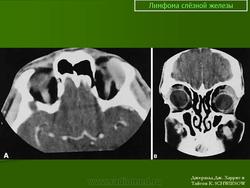

Диагноз злокачественной лимфомы орбиты труден. Из инструментальных методов исследования более информативны ультразвуковое сканирование, компьютерная томография (рис. 20.24, в) и тонкоигольная аспирационная биопсия с цитологическим исследованием. Необходимо обследование у гематолога для исключения системного поражения. Наружное облучение орбиты — практически безальтернативный высокоэффективный метод лечения. Полихимиотерапию подключают при системном поражении. Эффект лечения проявляется в регрессии симптомов патологического процеса в орбите и восстановлении утраченного зрения. Прогноз при первичной злокачественной лимфоме для жизни и зрения благоприятный (83 % больных переживают 5-летний период). Прогноз для жизни резко ухудшается при диссеминированных формах, но частота поражения орбиты при последних составляет чуть более 5 %.